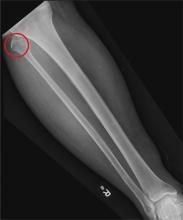

A 50-year-old man is brought to your facility by EMS personnel for evaluation after a motor vehicle crash. He was an unrestrained driver who swerved suddenly to avoid hitting a deer that jumped in front of him. He lost control of his vehicle, which rolled over several times and eventually landed in a ditch. His airbag deployed. The patient’s primary complaint is neck and right leg pain. His medical history is essentially unremarkable. He is awake, alert, and oriented, with stable vital signs. Primary survey shows a large laceration of his right leg over the tibia, with extensive soft-tissue injury and loss through the muscle. He has good range of motion in his knee, with no evident pain or swelling. His ankle and foot also show no injury and appear to be neurovascularly intact. You obtain a radiograph of the right tibia. What is your impression?

The radiograph shows a nondisplaced fracture of the proximal fibular head. No other fractures are evident. There is some evidence of soft-tissue injury and edema over the tibia.

An orthopedics consultation was obtained, with the presumption that the fracture would be nonsurgically managed.